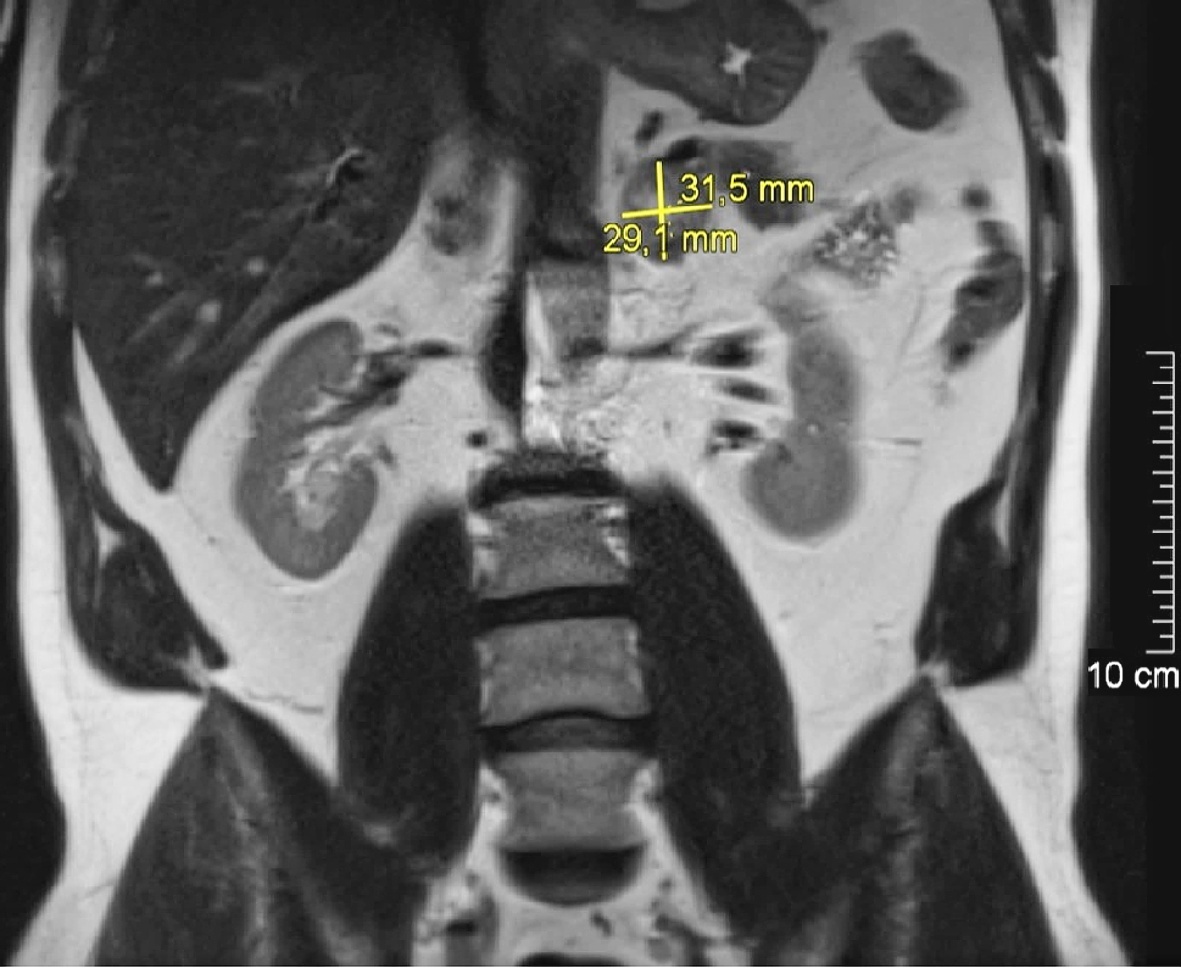

linken Nebenniere (Quelle: Klinik für Radiologie, BwZKrhs

Koblenz)

Auf Grund der Normetanephrinerhöhung erfolgte ein MRT der Nieren beidseits, welches die Diagnose eines Phäochromozytoms der Nebenniere links erbrachte (Abbildung 1).